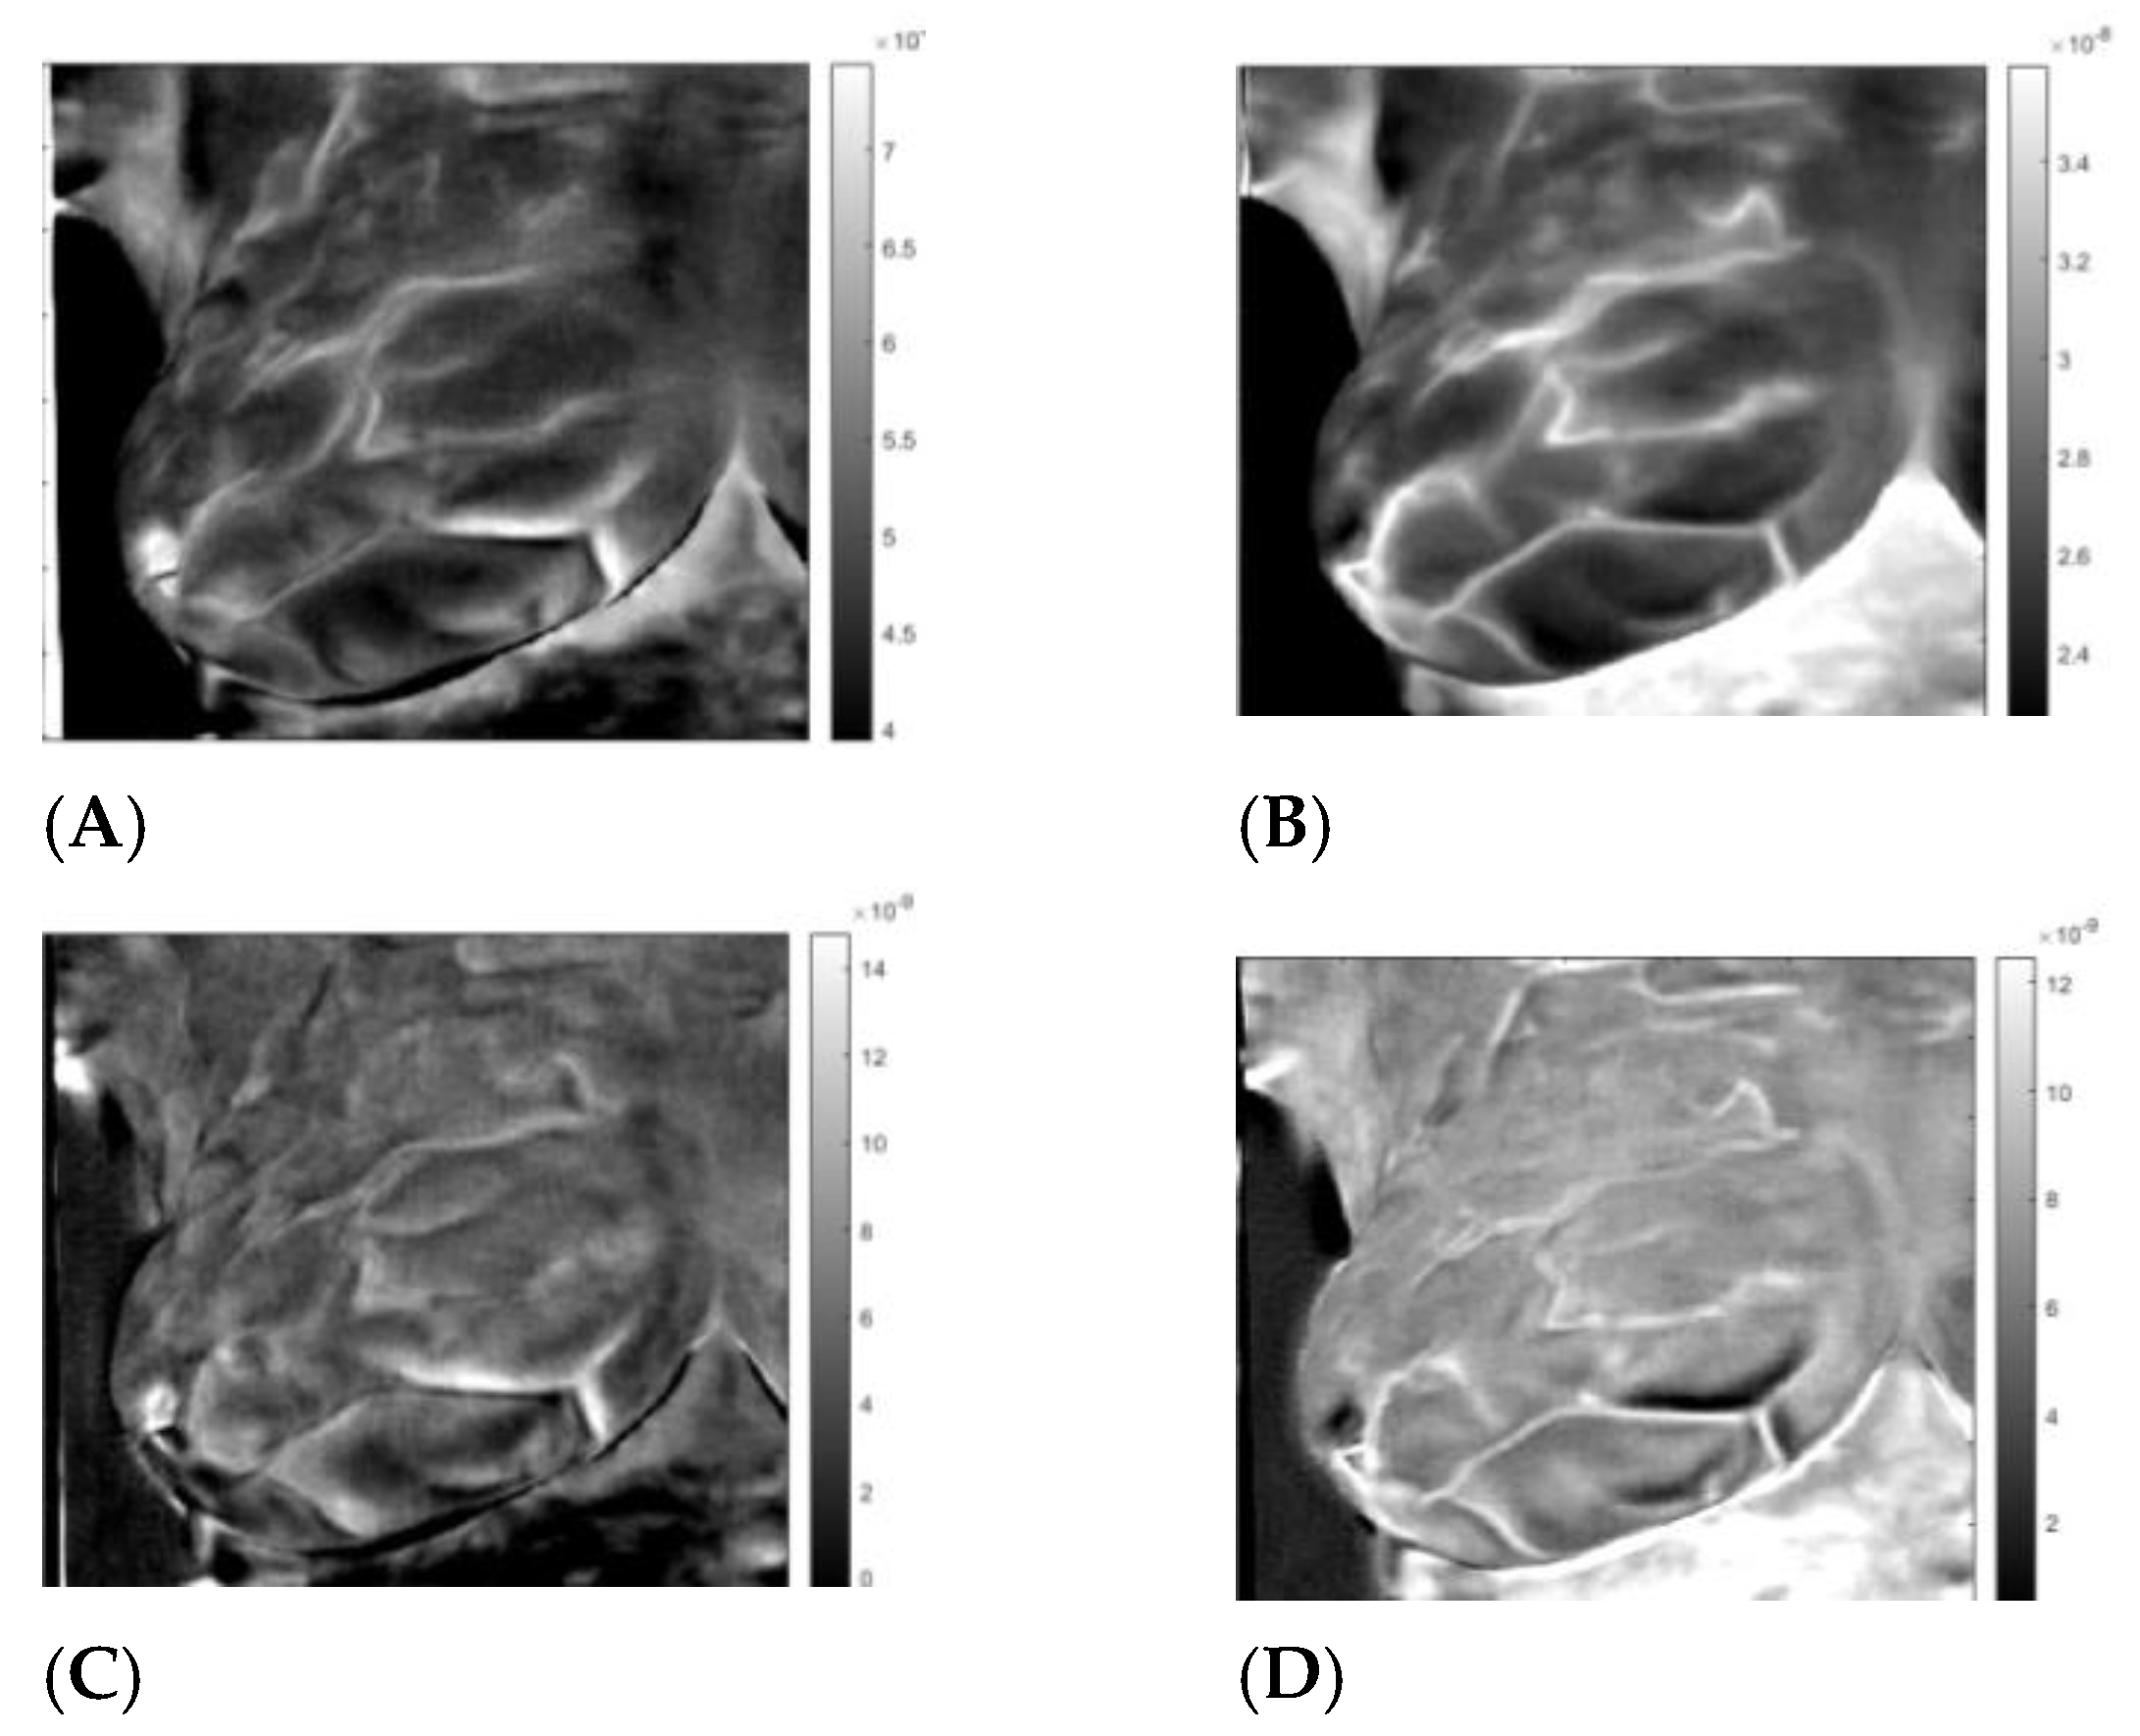

3. Results

3.3. Analysis